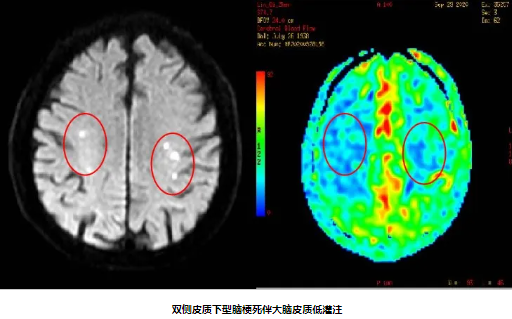

82岁男性,因“双下肢无力10天”入院,既往有“高血压病”史10年。入院后完善颈动脉彩超及影像学检查提示:1.分水岭梗死(双侧皮质下型)2.双侧颈内动脉重度狭窄 3.窦性心动过缓。经颈动脉狭窄MDT团队充分讨论,精心安排,在心血管内科中心的协助下,脑血管病专科团队克服了患者高龄、心动过缓等危险因素,成功给予患者双侧颈动脉支架同期植入,患者症状得到明显好转。